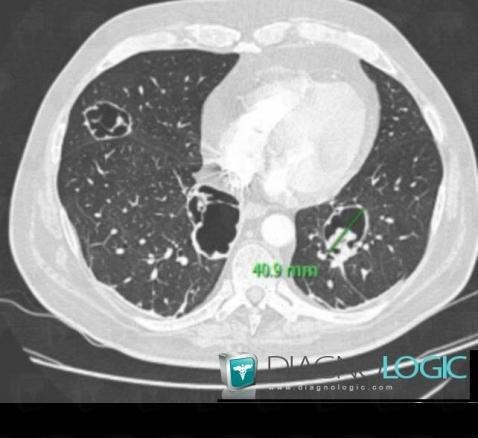

Pneumocystosis, Pulmonary parenchyma, CT

Here is the specific information in the key image above:

- Diagnosis Pneumocystosis, Location(s) Pulmonary parenchyma, with gamuts Cavitary pulmonary mass, Multiple pulmonary masses